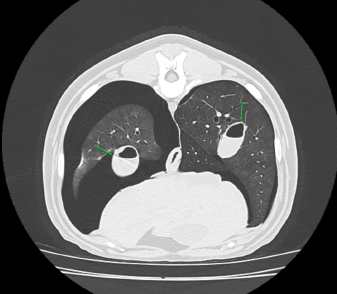

No complication due to ABP was observed. Control thoracic X-rays were obtained 24 hours and 1 week after the procedures, which did not show any signs of relapse in dogs 1 through to 4 (Fig. 4).

Fig. 4. Right-lateral thoracic radiographic of the same dog in Figure 3, 24 hours after autologous blood patch pleurodesis.